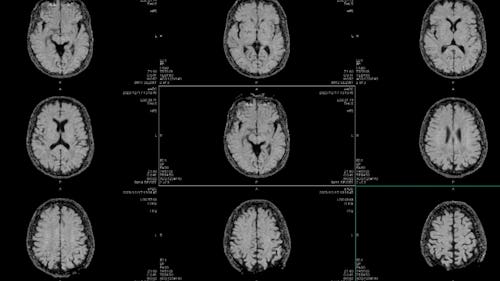

Using brain tissue from over 2,500 donors, researchers have built gene regulation networks that help outline multiple areas of the brain that play key roles in decision-making, memory, learning, emotion, reward processing, and motor control. They then created maps across different stages of brain development, and brain-related disorders. The findings were published across 15 different papers in Science, Science Advances, and Scientific Reports

In this work, researchers were able to develop population wide analyses, as well as single-cell maps of the prefrontal cortex. They also conducted experimental analyses that validated certain segments of DNA that are linked with observable traits.